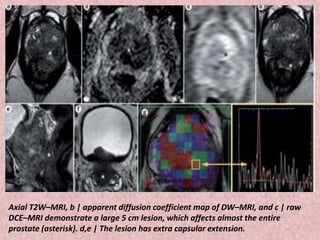

Axial T2W–MRI, b | apparent diffusion coefficient map of DW–MRI, and c | raw

DCE–MRI demonstrate a large 5 cm lesion, which affects almost the entire

prostate (asterisk). d,e | The lesion has extra capsular extension.